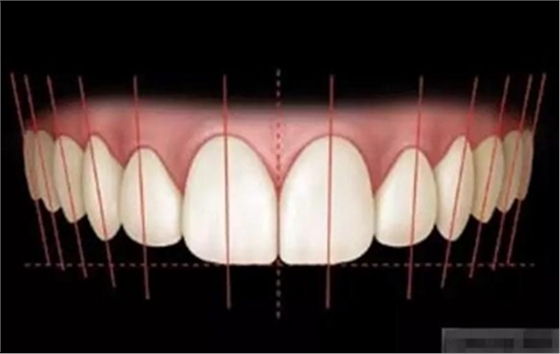

審美序列清單:

1、切牙的位置長(zhǎng)度

3.牙齒寬度

前牙的黃金分割比例

正面觀

側(cè)切牙約為中切牙的60%

尖牙約為側(cè)切牙的60%

5.外展隙:切端.頸部.唇側(cè)和舌側(cè)

6。發(fā)育葉和明度

7、表面光澤